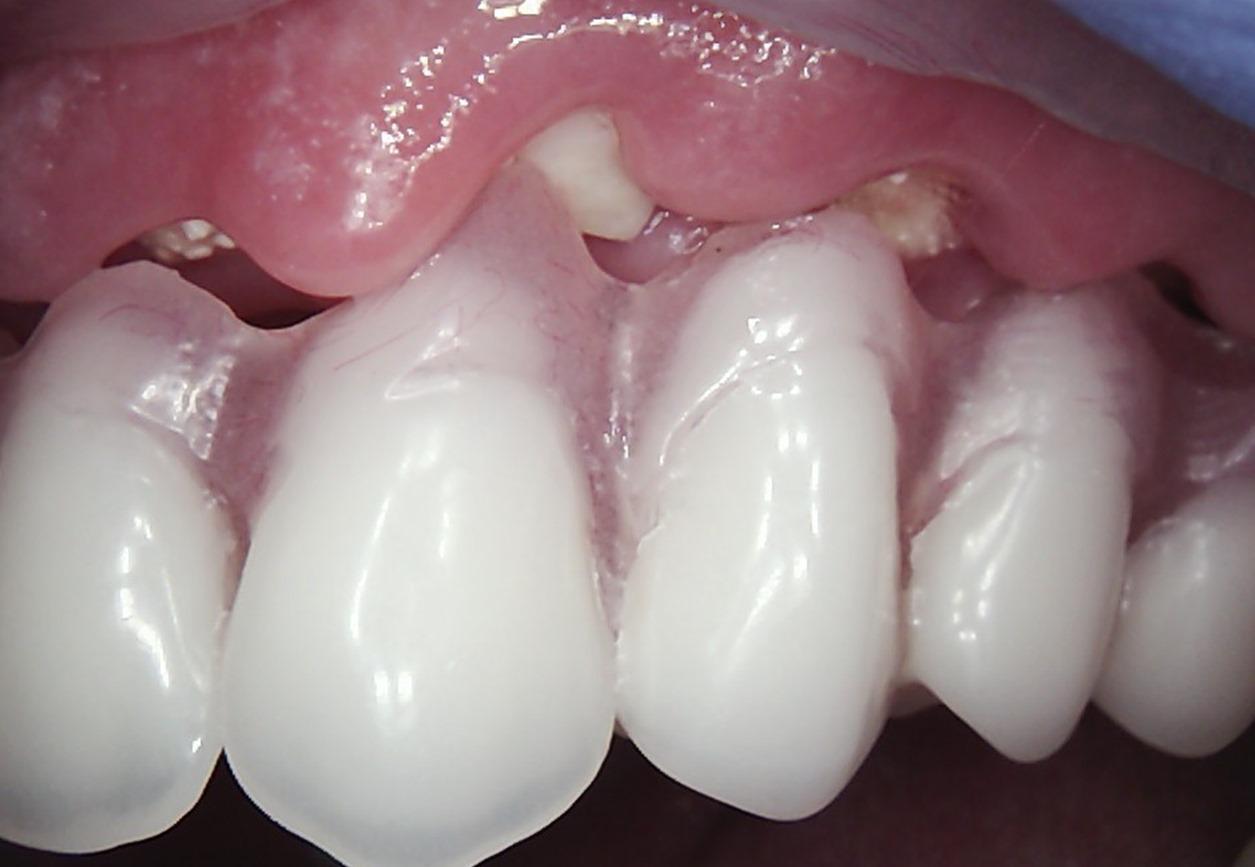

Long-term psychoactive substance use had caused severe xerostomia, contributing to the rapid development of dental caries and decay. The teeth in the upper jaw were non-restorable, and many were already missing. The condition of the lower jaw was slightly better: the anterior teeth were in satisfactory condition, but the posterior teeth were severely decayed and required extraction.

The presented images show the patient’s initial dental condition.